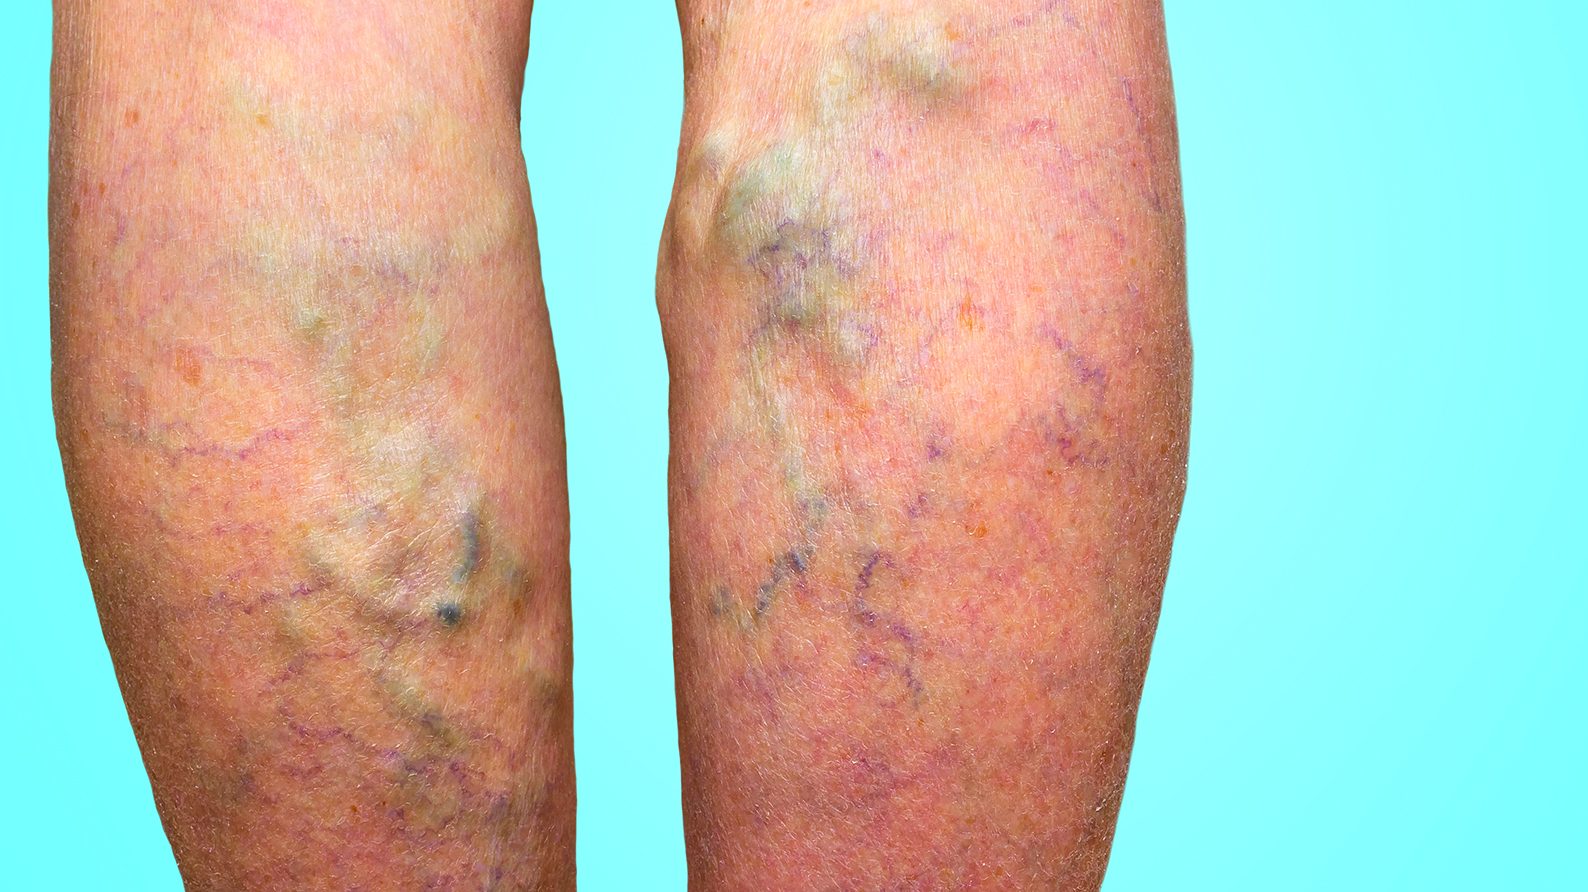

Les varices sont des veines irréversiblement endommagées; le sang peine à retourner vers le cœur et s’accumule dans celles-ci, ce qui entraîne leur dilatation. Si elles ne sont pas traitées,